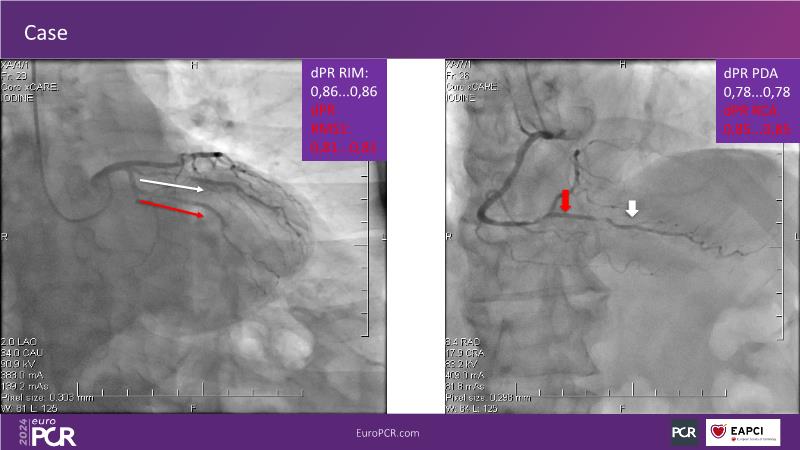

Physiology guided post-DCB treatment to safely limit stenting. Validation in complex clinical settings with the optical Optowire III pressure guidewire

Follow this session to discover how accurate resting index can inform decision-making for DCB in CTO patients and understand the role of physiology in a new PCI workflow for complex MVD. Thus, you will learn about a DCB intention-to-treat strategy guided by post-PCI coronary physiology in complex lesions, review new procedural techniques and workflows from real-world cases, and explore the pros and cons of this novel approach.

- To learn about DCB intention-to-treat strategy guided by post-PCI coronary physiology in complex lesions

- To review new procedural technique and workflow from real world patient cases